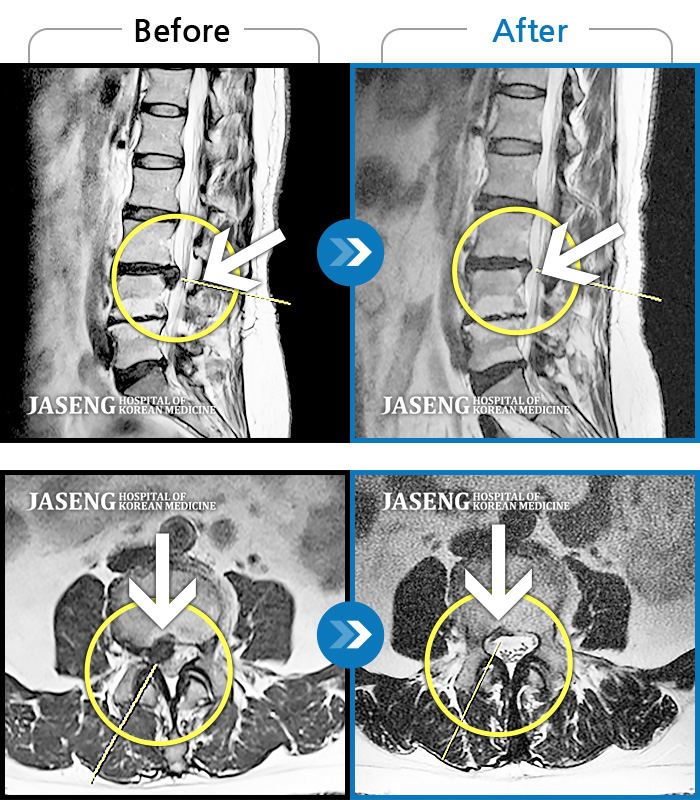

Before

After

환자에게 사전 동의를 받아 동일 조건에서 촬영되었습니다.

개인에 따라 치료 후 부작용이 발생할 수 있으니 의료진과 상담 후 치료를 진행하시기 바랍니다.

왼쪽 허리에서 다리로 내려가는 심한 통증과 하지의 근력 저하가 나타나 편하게 걷지 못하였습니다.

허리 양측부터 골반까지 통증, 자세 변경 시 증상 심화